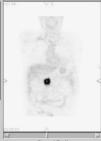

La tomografía por emisión de positrones permite la realización de un rastreo de «cuerpo entero» que tiene la ventaja de poder demostrar metástasis a distancia en lugares insospechados que modifiquen la indicación terapéutica en algunos casos65. Por otra parte, la tomografía por emisión de positrones (PET) es especialmente útil en el seguimiento de los pacientes con cáncer de páncreas, en los que las alteraciones anatómicas posterapéuticas dificultan la valoración locorregional de la recidiva tumoral en los estudios de TC y RM (fig. 13). En los casos en los que estas técnicas muestran hallazgos poco concluyentes, la PET tiene una clara indicación66. La posibilidad de combinar un equipo de PET con un equipo de TC (PET/TC)67 abre nuevas expectativas para el diagnóstico, estadificación y seguimiento del adenocarcinoma ductal pancreático.

Fig. 13.--Tomografía por emisión de positrones. Reconstrucción coronal que muestra una intensa captación de fluorodesoxiglucosa en el lecho quirúrgico, correspondiente a una recidiva tumoral en un paciente tratado mediante duodenopancreatectomía cefálica.